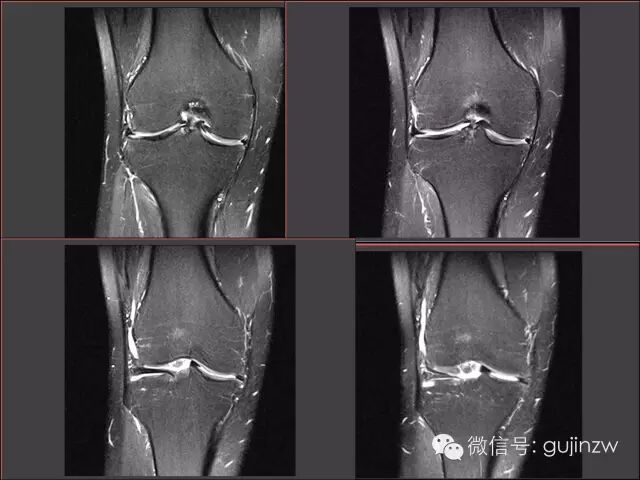

病例2

• 男,24岁。

• 主诉:打羽毛球扭伤致右膝关节疼痛活动受限1天。

• 症状:右膝关节疼痛,活动受限,交锁,伴弹响。

• 体征:膝关节活动度:15-120度,浮髌试验弱阴性,内外侧关节间隙无压痛。

• 被动挤压:麦氏征(+),Apley征(+)。

• 主动挤压:Ege‘s征(+),Thessaly 20°征(+)。

MRI